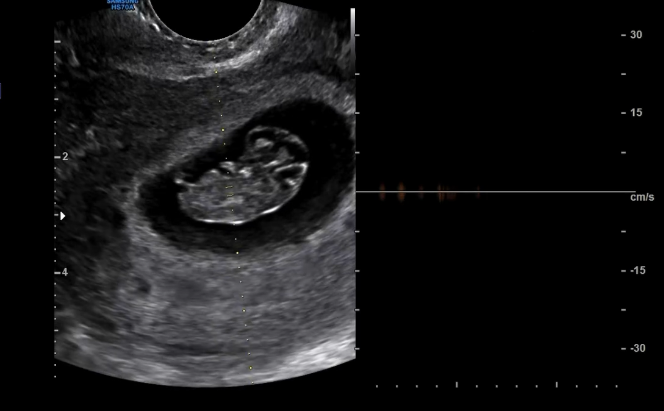

ทำเอาแฟนๆเเละคนในวงการต่างแสดงความยินดีกันอย่างมากเมื่อล่าสุดนักร้องสาวและอดีตไอดอล โกอูรี ออกมาประกาศข่าวดีครั้งใหญ่ในชีวิตว่า กำลังตั้งครรภ์ลูกคนแรกผ่านรายการดัง พร้อมบอกว่าอายุครรภ์อยู่ที่ประมาณ 7 สัปดาห์แล้ว